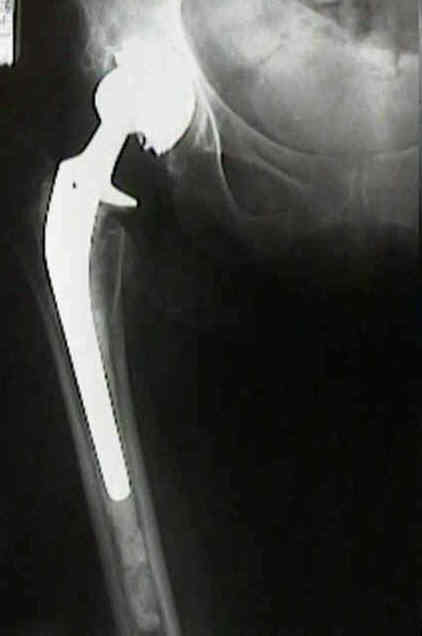

Loosening of Press Fit Acetabular Components

radiographic signs of loosening

- radiolucent lines that initially appeared after two years

- progression of radiolucent lines after two years

- radiolucent lines in all three zones

- radiolucent lines 2 mm or wider in any zone

- migration

- loosening is present w/ more than 2 mm of migration (either horizontal or vertical);

- continuous radiolucent line;

- note that peripheral radiolucent lines which are non-continuous are commonly found in press fit acetabular components and are often not progressive;